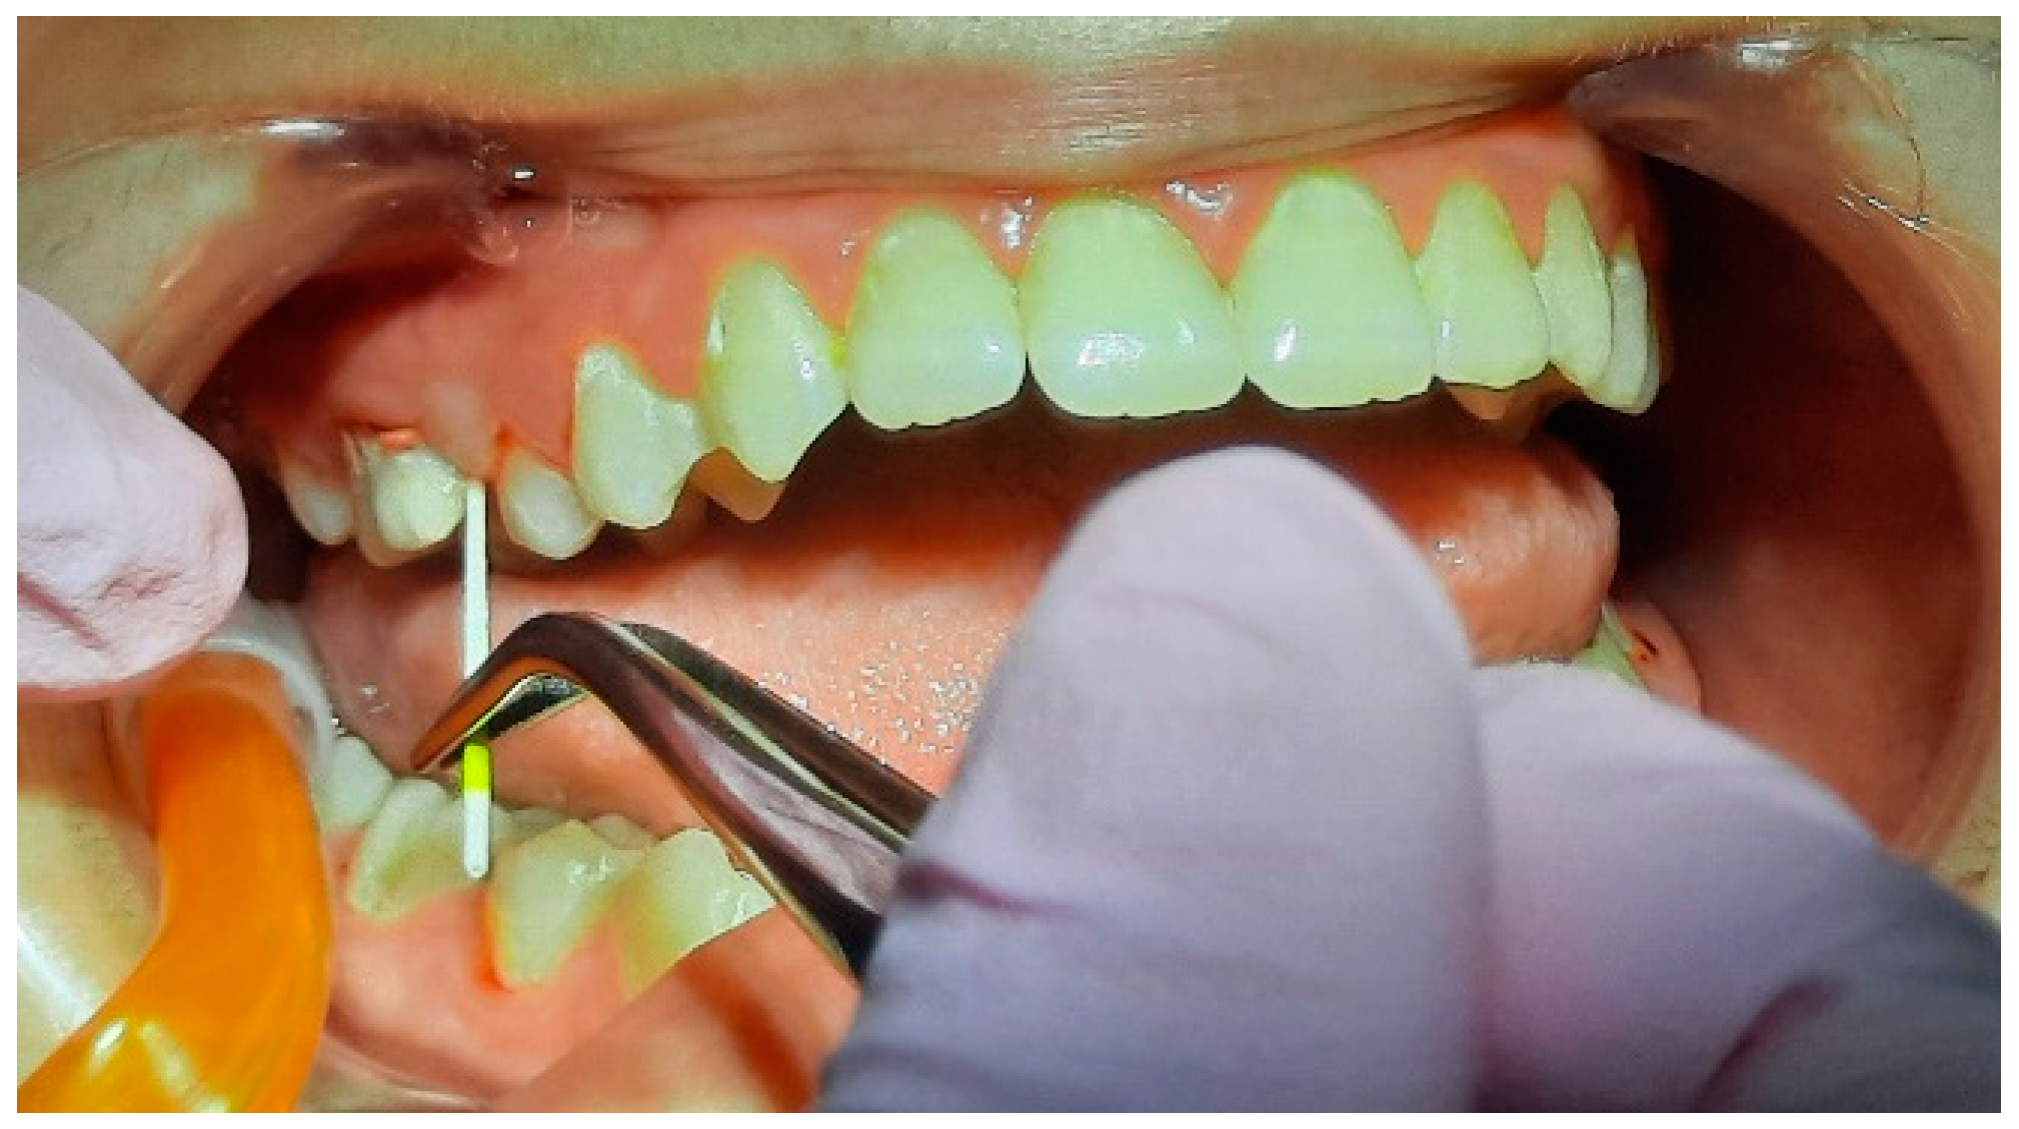

2.2. Clinical Examinations

2.3. Sampling for PCR

2.5. Specialist Treatment